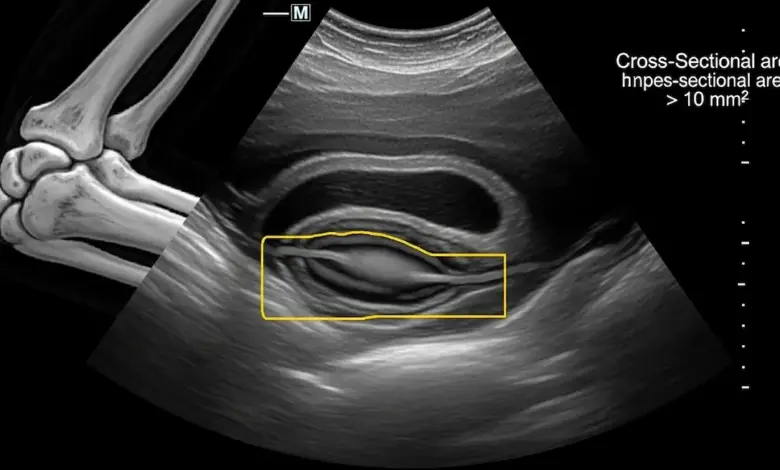

- Ultrassonografia para visualizar espessamento do nervo ou instabilidade dele durante a flexão do cotovelo.